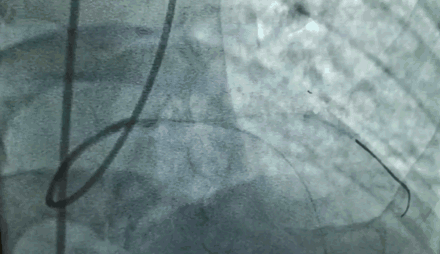

67岁女性,主动瓣左冠窦腔小,严重钙化,主动脉宽,冠状动脉开口位置低,手术条件恶劣。

“所有不好的指标全在一个病人身上,很麻烦。”

冠状动脉开口位置的高度相对较低,是决定病人能不能做TAVR手术的非常重要的因素。如果冠状动脉开口比较低,有可能瓣膜植入之后会挡住冠状动脉开口,引起急性心梗,这将是一个灾难性的后果。

对于这种棘手病例,来永强教授团队从来都是选择迎难而上。

术前就和周玉杰教授团队做了周密研讨和细致评估,包括体外模拟植入瓣膜后的冠脉情况。术中,也做了多种应急预案,一方面备了体外循环机器,万一不行,就转机上体外循环支持;另一方面,在左冠主干的位置放了导丝,如果造成左冠动脉缺血,会立即行冠状动脉球囊扩张➕支架植入治疗。

在瓣膜的选择上,也充分考虑到冠脉开口位置低、主动瓣左冠的窦部比较小的问题,最终采用16mm球囊预扩,20mm瓣膜释放,一个半小时左右的手术过程顺利,冠状动脉开口没有受到影响,冠脉的供血也比较好。

可以说,这台的成功得益于术前充分的会诊、讨论、风险评估,防止一切发生风险的因素,这不仅仅是一台高难度手术,更是多学科协作的成功典范。